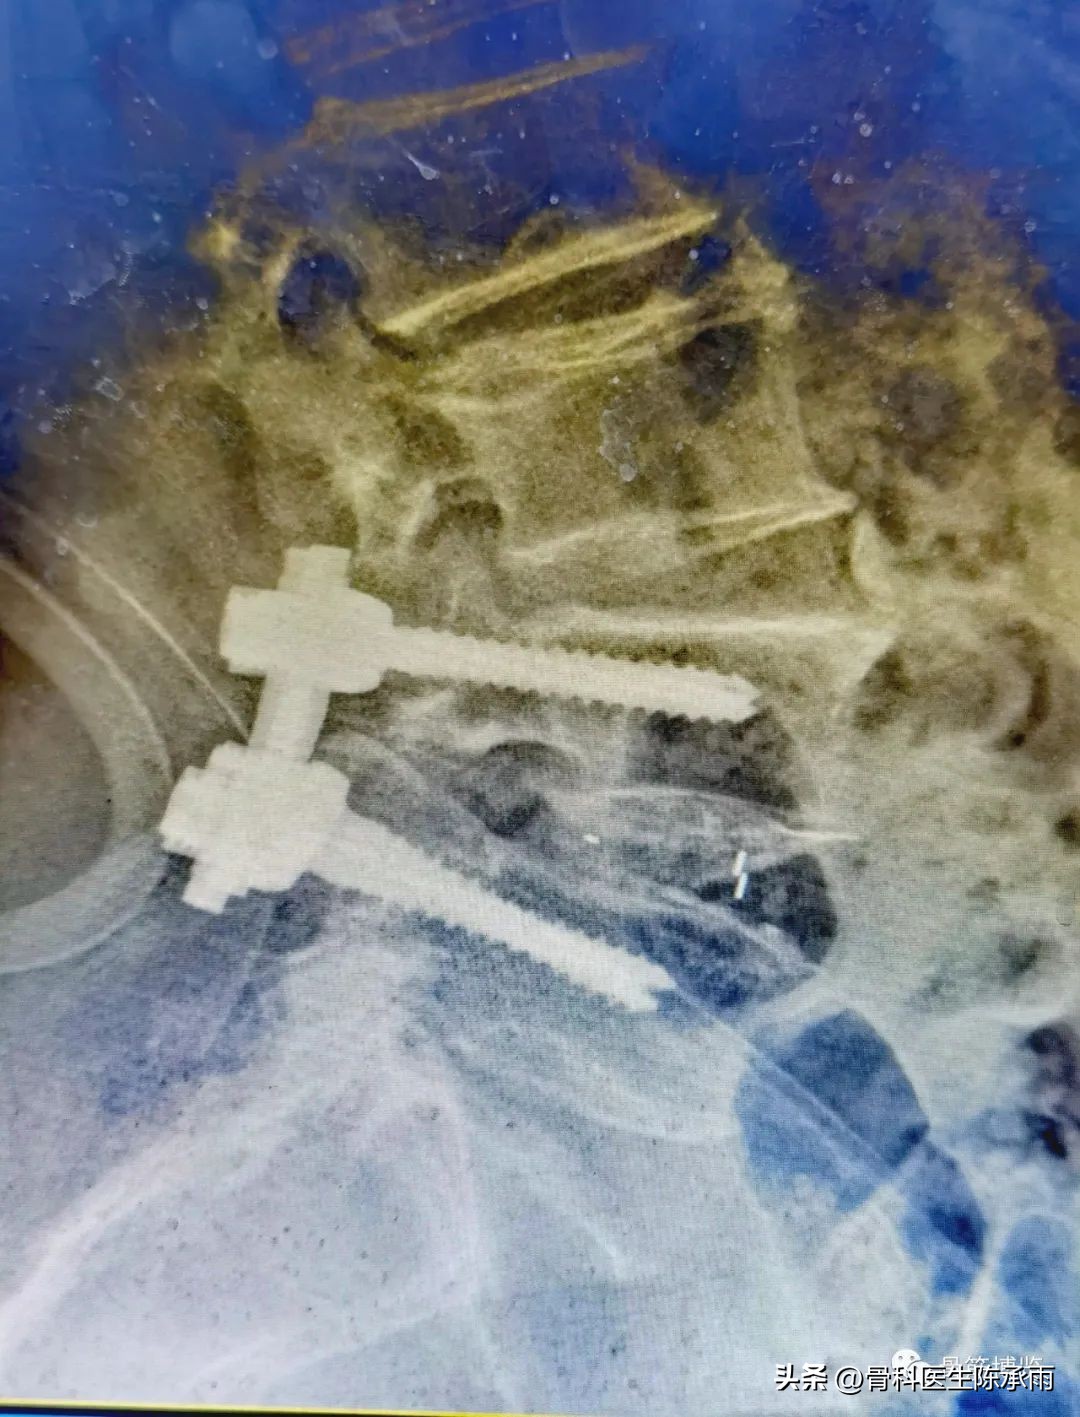

1例 腰椎滑脱伴椎管狭窄

术前影像